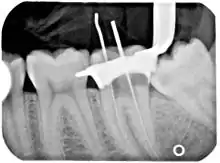

An x-ray of a root canal operation

Before endodontic therapy is carried out, a correct diagnosis of the dental pulp and the surrounding periapical tissues is required. This allows the endodontist to choose the most appropriate treatment option, allowing preservation and longevity of the tooth and surrounding tissues. Treatment options for an irreversibly inflamed pulp (irreversible pulpitis) include either extraction of the tooth or removal of the pulp.

Removing the infected/inflamed pulpal tissue enables the endodontist to help preserve the longevity and function of the tooth. The treatment option chosen involves taking into account the expected prognosis of the tooth, as well as the patient's wishes. A full history is required (which includes the patient's symptoms and medical history), along with a clinical examination (both inside and outside the mouth), and the use of diagnostic tests.[8]